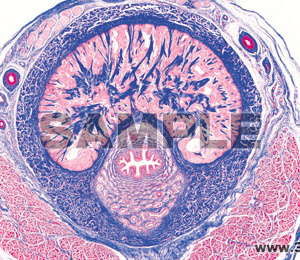

- 1(d) ラットの精巣,精子形成を表示する横断面

- 4(d) ブタまたはウサギの精索(横断)

- 7(d) ウサギの陰茎(横断)